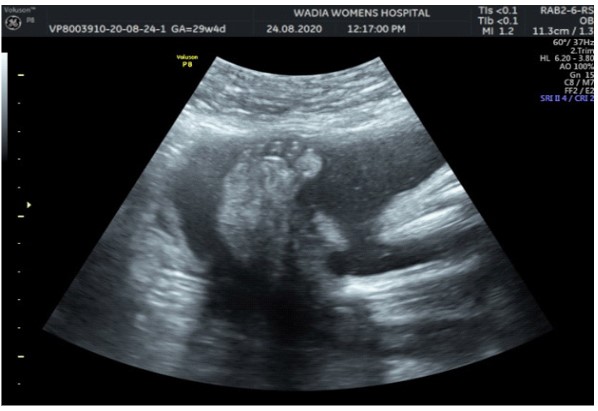

In the third conception during the COVID-19 pandemic, the couple presented to us in the third trimester. Anomaly screening ultrasound at 18 weeks done elsewhere was unremarkable, but subsequent scan done at our institute at 29 weeks was suggestive of fetal biometry corresponding to 26 weeks, head circumference below 1st centile, composite growth along 3rd centile. The fetus had microcephaly and sloping forehead; head circumference measured 241 mm (less than 1st centile for gestational age) (Figure 1). Transcerebellar diameter measured 23.6 mm (<1st centile) with vermis spared suggestive of cerebellar hypoplasia (Figure 2). The Cavum Septum Pellucidum (CSP) was enlarged measuring 22 mm x 10 mm (Figure 3). Additional ultrasound findings were corpus callosum agenesis, kinked thalami, widened subdural spaces and right club foot (Figure 4). The ultrasound differentials were pontocerebellar hypoplasia or Walker Warburg syndrome.